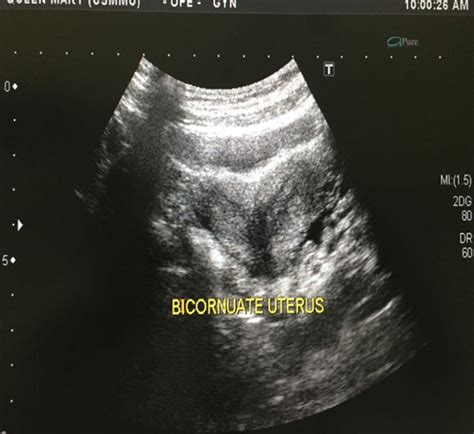

Uterus didelphys, commonly referred to as a “double uterus,” is a congenital condition where the uterus is present as two separate organs, each with its own cervix and often a duplicated vagina. This anomaly occurs during fetal development when the Müllerian ducts—the structures that eventually form the female reproductive tract—fail to fuse together completely. Instead of forming a single, pear-shaped uterus, they develop into two separate, smaller uterine cavities.

Physicians use advanced imaging to confirm the diagnosis. If you are looking at Didelphic Uterus Images for reference, you will notice the clear separation of the two uterine horns. Common diagnostic tools include:

Transvaginal Ultrasound Initial screening and visualization High for initial detection